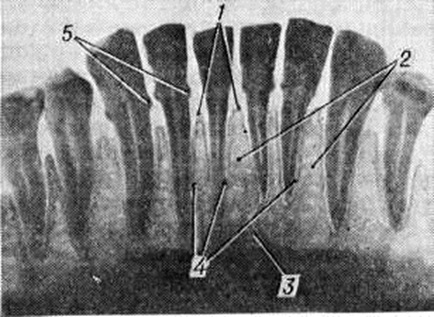

Рентгенологические картина Пародонтоз зависит от стадии процесса. В начальной стадии выявляются остеопороз (смотри полный свод знаний) и деструкция коркового вещества вершин межальвеолярных перегородок. В развившейся стадии отмечается усеченность вершин межальвеолярных перегородок, наряду с горизонтальной появляется и вертикальная резорбция, нередко с образованием костных карманов. Контуры альвеолярных отростков имеют характерный фестончатый, «изъеденный» вид (рис. 4), определяется отложение поддесневого зубного камня. Нарастание патологический процесса проявляется появлением очагов пятнистого остеопороза и образованием костных абсцессов. Стадия стабилизации рентгенологически проявляется уплотнением контуров гребней межальвеолярных перегородок, исчезновением очагов пятнистого остеопороза.

Рентгенологические картина Пародонтоз с преобладанием дистрофических изменений в пародонте характеризуется равномерным снижением высоты межальвеолярных костных перегородок, склерозированием костной ткани альвеолярного отростка, сужением периодонтальной щели (рисунок 5).